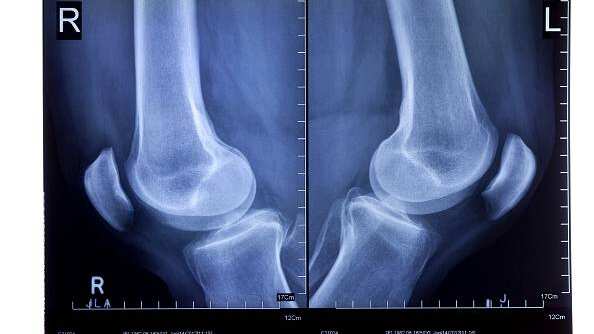

Acorde a una investigación de la Escuela Imperial de Londres, se trata de la fabela, el cual es un pequeño hueso que se encuentra incrustado en un tendón detrás de la rodilla.

Sin embargo, para el 2018 el hueso se encontraba en el 39% de la población mundial, algo que los científicos no logran comprender, tomando en cuenta además que los expertos tampoco logran dilucidar cuál es la función de la fabela.